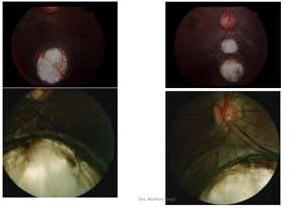

Figura 2: Neurorretinitis por Bartonella

• Trombosis Venosa Retinal: Puede ser de vena central o alguna de sus ramas. Mayores de 70 años, Hipertensión, Diabetes Mellitus e Hipertensión Ocular son los principales factores de riesgo. El diagnóstico se hace por el fondo de ojo, donde se observan hemorragias retinales en llama, con vasos venosos engrosados y tortuosos. Puede haber DPAR. No tiene tratamiento agudo, pero la evaluación por oftalmólogo es fundamental para el manejo de complicaciones.

Trombosis de Vena Central de la Retina

Atrofia Macular en DMRE Seca.